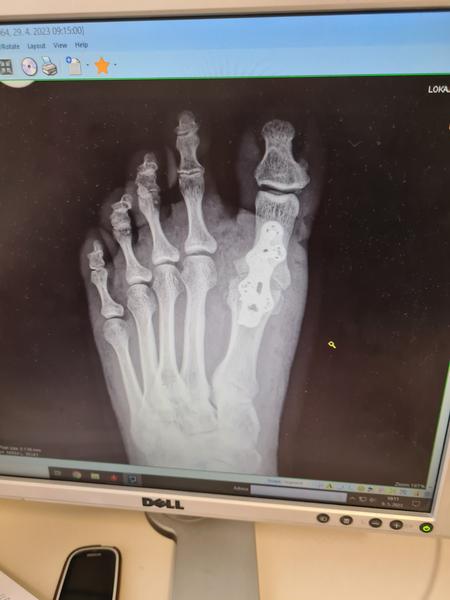

@simsalabim ano je to tak. Mam tam toto..a je nad zemou .nedotýka sa inak by si zakopavala

@simsalabim takto to je znehybnene,dlahou a srobami